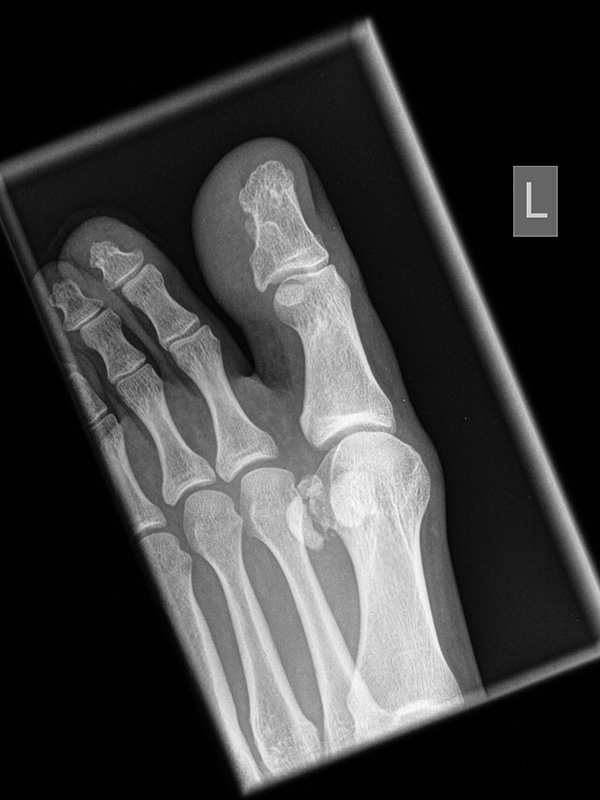

Fuß dp (dorsoplantar) mit Belastung

Positionierung:

• Der Patient steht unter gleichmäßiger Gewichtsbelastung auf beiden Füßen.

• Die Fußachse ist nach vorne gerichtet.

• Die Kassette liegt unter dem zu röntgenden Fuß.

• Der Zentralstrahl wird auf das Tarsometatarsalgelenk II zentriert.

• Die Röntgenröhre ist 15° vertikal gekippt.

• Anmerkung: Technisch lässt sich die Röhre beim stehenden Patienten nicht in 0° über dem Fuß positionieren. Eine Kippung der Röhre um 15° erlaubt darüber hinaus eine bessere Einsicht in die tarsometatarsalen Gelenke.

Kennzeichen des Röntgenbildes:

• Standardabbildung des Fußes zusammen mit der belasteten seitlichen Aufnahme und der unbelasteten Schrägaufnahme.

• Die belasteten Aufnahmen liefern relevante Informationen zur Fußstatik und sind die Grundlage aller achskorrigierenden Eingriffe an Vor- und Rückfuß.

• Sämtliche Winkelbestimmungen beziehen sich auf belastete Aufnahmen.

Besondere Bemerkungen zum Beispielbild:

• Schwere Hallux valgus Deformität.

• Die Sesambeine sind luxiert, ebenso das Großzehengrundgelenk. Luxation des Metatarsophalangealgelenks II.

• Degenerative Veränderungen der tarsometatarsalen (TMT) Gelenkreihe, betont TMT II und III.

Zur Vollansicht und zum Lesen der Bildbeschreibung bitte die Bilder anklicken.

Fuß seitlich mit Belastung

• Der Patient steht auf beiden Füßen mit gleichmäßiger Lastverteilung.

• Der zur Röntgen der Fuß wird längs des Films positioniert.

• Die Kassette steht senkrecht zum Boden, medial dem Fuß anliegend.

• Der Zentralstrahl wird von lateral nach medial zentriert auf das Kalkaneokuboidalgelenk knapp cranial der Os metatarsale V Basis ausgerichtet.

• Die Röntgenröhre steht 0° horizontal.

• Standardabbildung des Fußes zusammen mit der belasteten d.-p. Aufnahme und der unbelasteten 45° Pronationsaufnahme.

• Überblick über die Fußanatomie und Fußstatik.

• Die seitliche Aufnahme liefert Informationen zur Stabilität des Längsgewölbe und zu den Achsen von Talus, Kalkaneus und Metatarsale I.

• Die Aufnahme wird eingesetzt zur Darstellung von freien Gelenkkörpern sowie knöchernen Veränderungen am Achillessehnenansatz oder der Plantarfaszie.